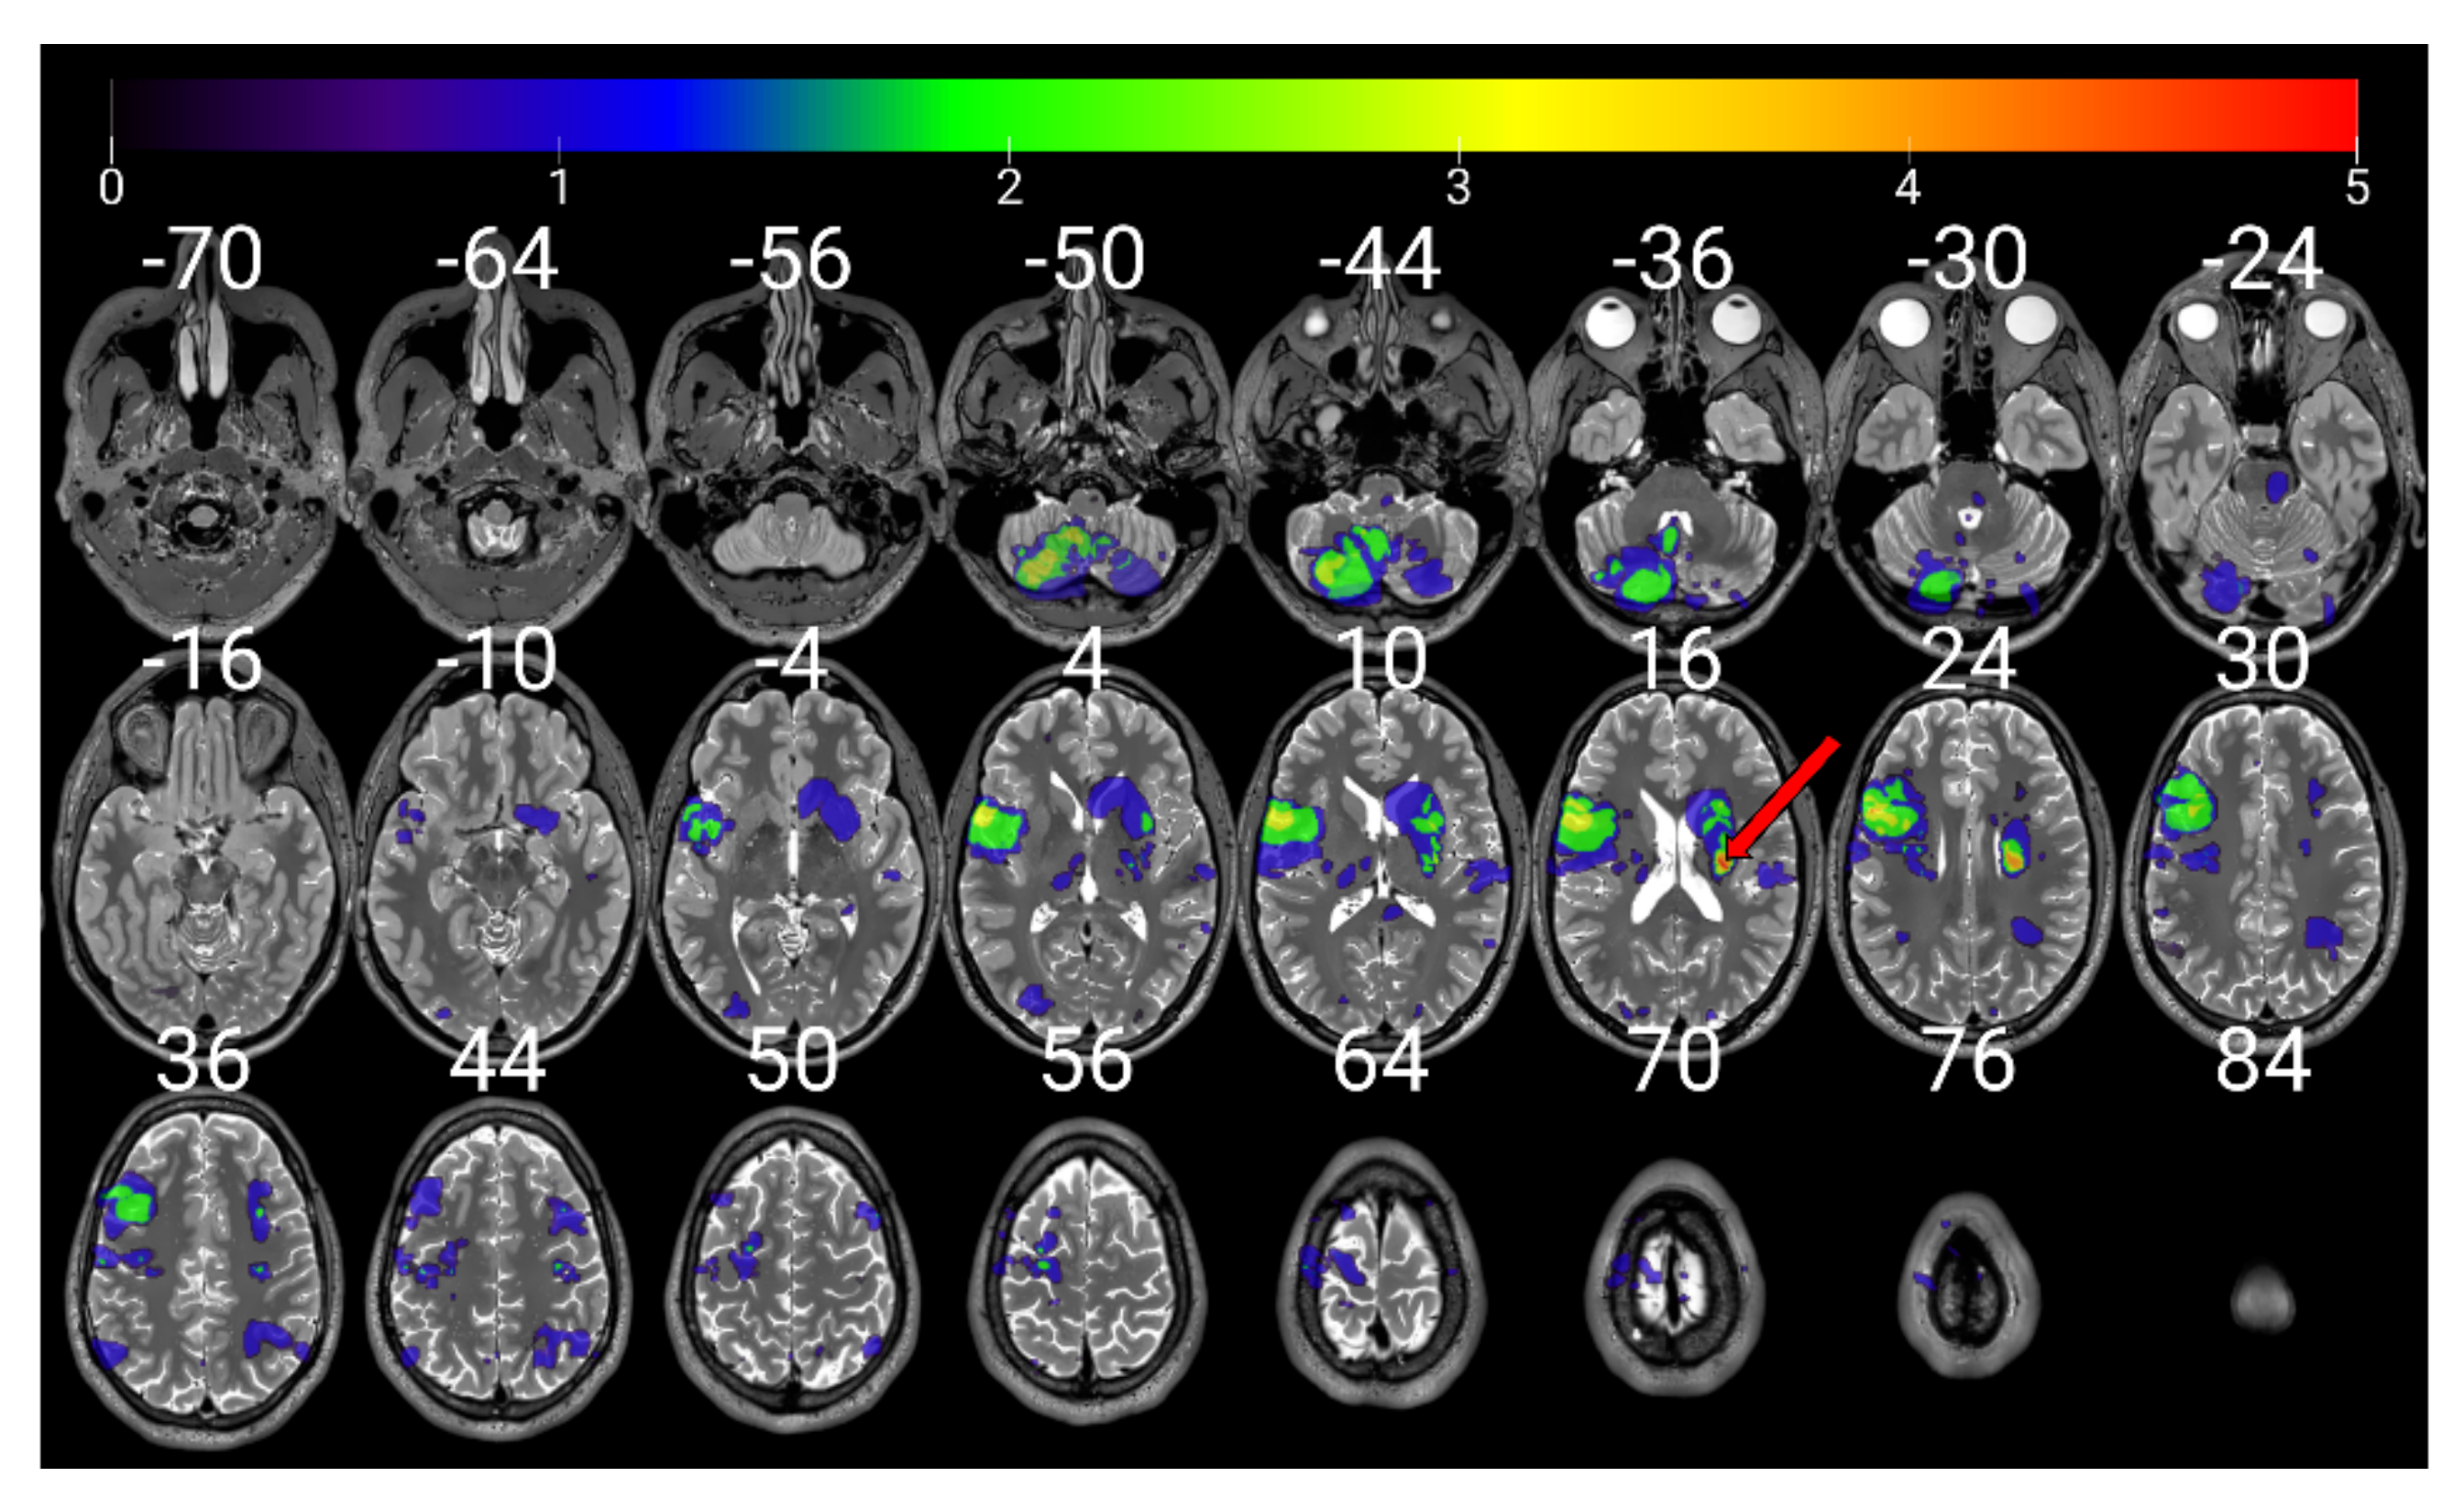

- Karnath, H.-O.; Sperber, C.; Wiesen, D.; de Haan, B. Lesion-Behavior Mapping in Cognitive Neuroscience: A Practical Guide to Univariate and Multivariate Approaches. In Spatial Learning and Attention Guidance; Pollmann, S., Ed.; Humana Press: New York, NY, YSA, 2019; pp. 1–37. [Google Scholar]

- Bates, E.; Wilson, S.M.; Saygin, A.P.; Dick, F.; Sereno, M.I.; Knight, R.T.; Dronker, N.F. Voxel-Based Lesion-Symptom Mapping. Nat. Neurosci. 2003, 6, 448–450. [Google Scholar] [CrossRef]

- De Haan, B.; Clas, P.; Juenger, H.; Wilke, M.; Karnath, H.O. Fast Semi-Automated Lesion Demarcation in Stroke. NeuroImage Clin. 2015, 9, 69–74. [Google Scholar] [CrossRef]

- Rorden, C.; Bonilha, L.; Fridriksson, J.; Bender, B.; Karnath, H.O. Age-Specific CT and MRI Templates for Spatial Normalization. Neuroimage 2012, 61, 957–965. [Google Scholar] [CrossRef]